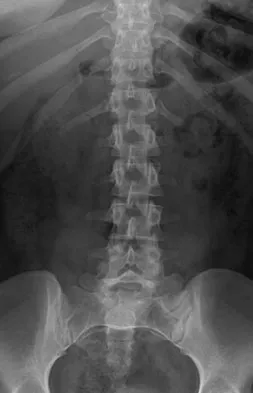

A 44-year-old woman has had lower extremity dysesthesias, urinary incontinence, and has been unable to walk for the past 2 days. She reports no pain or history of trauma. She notes that 3 weeks ago she missed work for 2 days because of back pain, but it resolved with rest. Examination shows decreased or absent sensation below the knees, no motor function below the knees, and decreased rectal tone. Catheterization results in a postvoid residual of 2,000 mL. Plain radiographs and MRI scans without contrast are shown in Figures 1a through 1d. What is the next most appropriate step in management?

Explanation

The patient has had a clear and sudden onset of a profound neurologic deficit. The radiographic studies suggest a lesion in the conus medullaris that appears to be intradural and intramedullary. MRI, with and without contrast, will best evaluate this mass further. The addition of gadolinium allows further evaluation of vascularity and the extent of the lesion. Eichler ME, Dacey RG: Intramedullary spinal cord tumors, in Bridwell KH, Dewald RL (eds): The Textbook of Spine Surgery, ed 2. Philadelphia, PA, Lippincott-Raven, 1997, vol 2, pp 2089-2116.